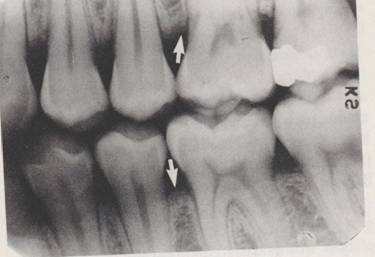

n Triangulatia

Afectarea concomitenta a septului si a extremitatii coronare a spatiului periodontal

Triunghi radiotransparent cu baza la nivelul crestei septului si varful orientat in sens apical spre spatiul periodontal. O latura spre radacina, cu contur net si alta septala, cu contur sters. Inaltimea triunghiului=1-2mm,

Lamina dura subtiata, disparuta

Creasta septului - ascutita